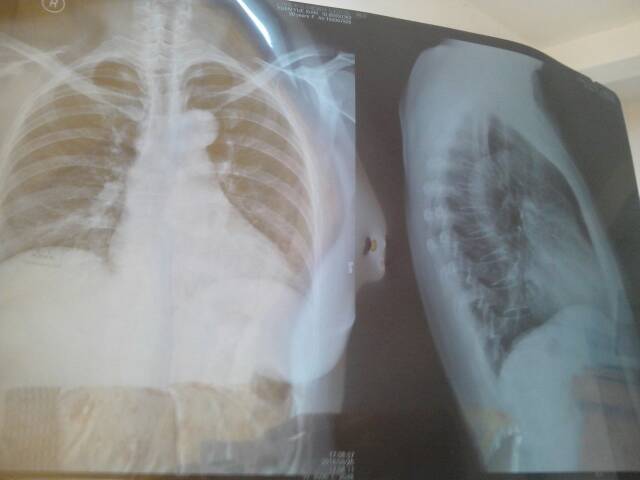

这是我母亲的片子,她今年50岁身体不好晚上睡觉呼噜呼噜响,喘不过气很难过。透片医生直叫做检查,但就不说怎么样了。有看得懂的请帮忙看一下谢了!